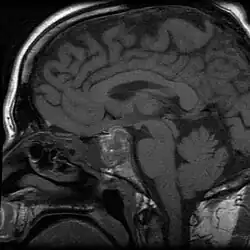

MRI of man with pituitary apoplexy

Apoplexy (from Ancient Greek ἀποπληξία (apoplexia) 'a striking away') refers to the rupture of an internal organ and the associated symptoms. Informally or metaphorically, the term apoplexy is associated with being furious, especially as "apoplectic". Historically, it described what is now known as a hemorrhagic stroke, typically involving a ruptured blood vessel in the brain; modern medicine typically specifies the anatomical location of the bleeding, such as cerebral apoplexy, ovarian apoplexy, or pituitary apoplexy.[1][2][3]